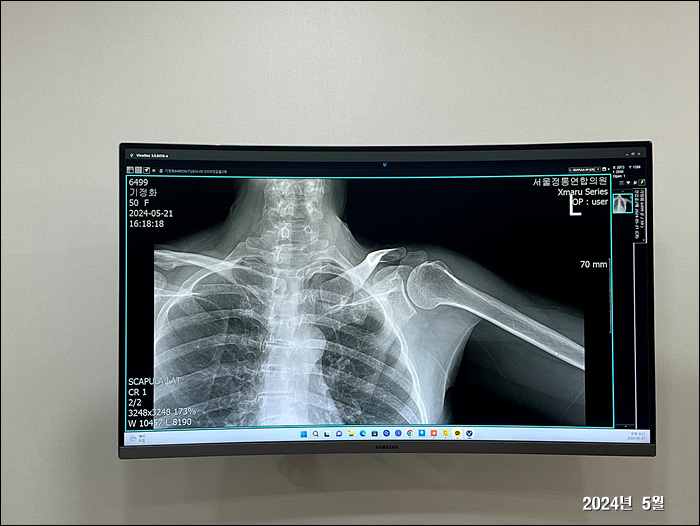

2024. 5. 21.

정화 오십견 진단

의정부에 일하러 갔다가... 병원가서 오십견 진단 받고옴.

팔이 갈수록 아파서 위로는 잠도 못자고... 힘든 하루 하루를 보내고 있음

2024. 5. 23.

왼쪽팔이.... 갈수로 굳어지고 아프다...=..=

이렇게 운동하면 좋다길래 밤마다 온가족이 나와서 운동기구로 팔을 풀어준다.